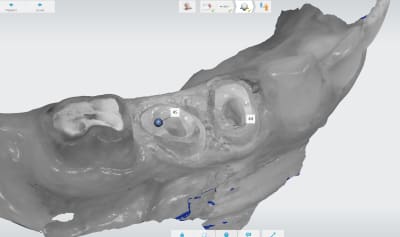

Pour que ça pisse pas trop. Loupes fois 5 pour éviter de toucher la gencive. Quand tu peux pas faire autrement expasyl si ca résiste laser. Ici en distal de 44.